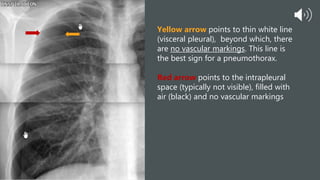

Yellow arrow points to thin white line

(visceral pleural), beyond which, there

are no vascular markings. This line is

the best sign for a pneumothorax.

Red arrow points to the intrapleural

space (typically not visible), filled with

air (black) and no vascular markings

Yellow arrow pointsto thin white line (visceral pleural), beyond which, there are no vascular markings. This line is the best sign for a pneumothorax. Red arrow points to the intrapleural space (typically not visible), filled with air (black) and no vascular markings

• #13 In this xray we see a faint, but distinctly visible opaque (white) line running along the lateral edge of the lung beyond which there are no vascular markings . This is the visceral pleura and the single best sign for a pneumothorax. The black stripe lateral to the white line is the intrapleural space, filled with air which appears black (red arrow). The visceral pleura is displaced medially. Typically we do not see a separation between the visceral and the parietal pleura a the space is tiny, but when air enters the space, a separation develops and this is the pneumothorax.